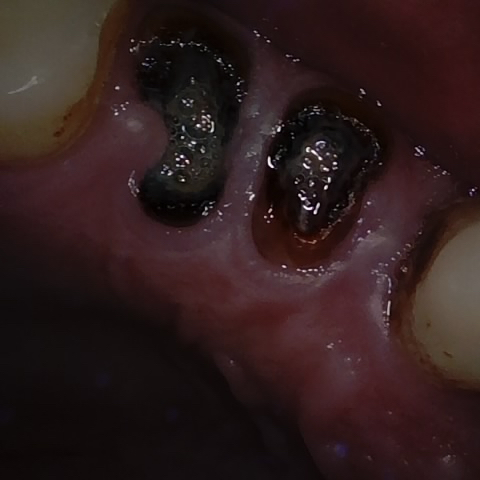

NHD36692

Annotated as "Good"